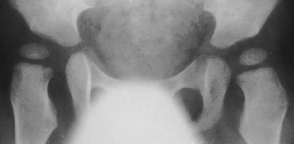

the subluxation progressed on x-ray.

Popleteal angle was 45 degrees and Thomas was 30 degrees bilaterally.

At 4y.+1m., he underwent soft tissue release:fractional lengthening

of proximal part of semitendinosus and biceps ; slide lengthening of semimembranosus;

tenotomy of adductor longus and Gracilis and psoas major; fractional lengthening

of rectus femoris and intermedius. An abduction pillow has been applied